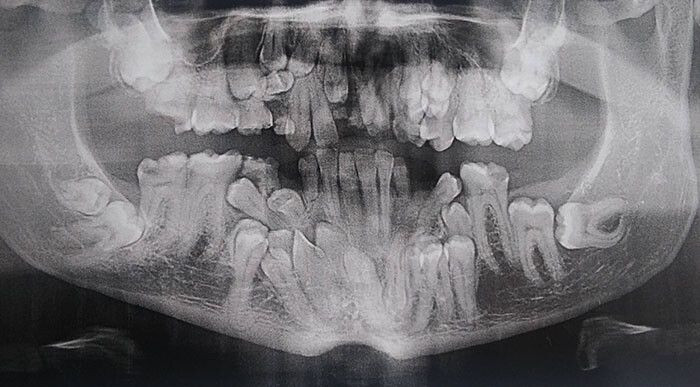

매복사랑니 4개 발치했습니다^^

아 사진 뭐임 진짜 혈압 확 오르네

???? 와 첫번째 사진은.. 오마이갓..

첫번째 사진….이가 왜저렇게 많으신가요…?